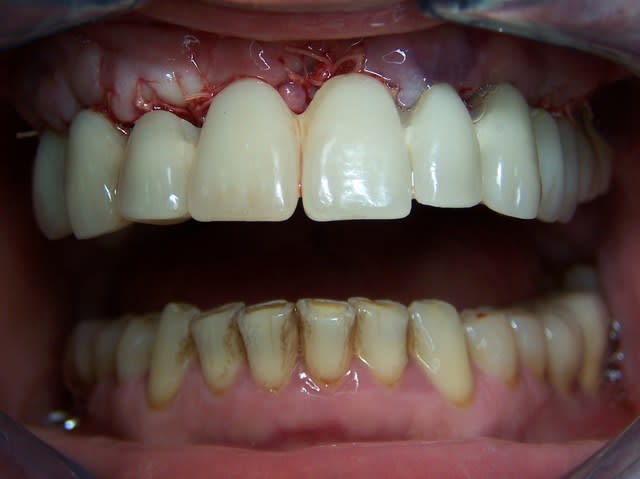

planif cas 1

contrôle d'un des cas à 1 mois

Je viens de revoir au cabinet un des 3 cas, car la céramique de la 25 était fracturée.

J'ai pris une photo (iphone) avec le bridge déposé avant de mettre temporairement le bridge coping de Posit. Pas la peine de commenter le bas je n'en suis pas responsable.